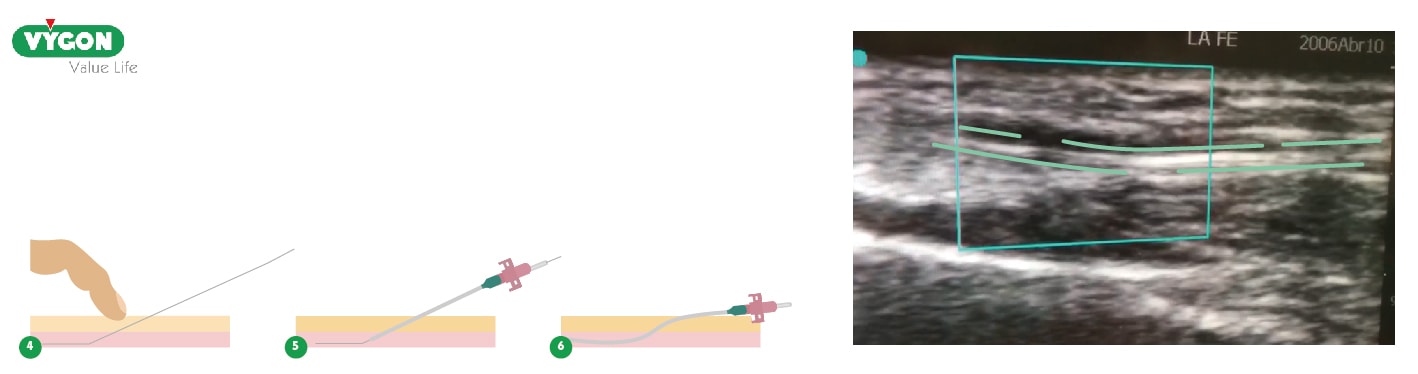

4. Realizar la punción ecoguiada “en plano” de la arteria radial

Se recomienda canalizar en plano, ya que a pesar resultar técnicamente más difícil, siempre es más fiable que canalizar fuera de plano.

La canalización en plano permite observar mejor la entrada de la aguja dentro de la arteria, además de poder observar si surge alguna complicación como la aparición de un hematoma o una disección de la pared arterial al pasar la guía.

Los pasos para realizar la canalización ecoguiada en plano serán los siguientes:

- Una vez identificada la arteria y el sitio de punción se recomienda, siempre que sea posible, girar la sonda ecográfica 90º y realizar la punción “en plano”.

- Al canular la arteria y observar el flujo pulsátil, a través de la aguja, procederemos a avanzar la guía metálica con suavidad.

5. Verificar la correcta posición del fiador en el interior de la arteria radial

Una vez canulada la arteria se deslizará la guía metálica a través de la aguja y se verifica con ultrasonido la correcta ubicación en el interior de la arteria utilizando la misma visión en “eje largo”.

6. Verificar la correcta posición del catéter en el interior de la arteria radial

Una vez comprobada la correcta colocación de la guía metálica en el interior de la arteria, retiramos la aguja e introducimos el catéter a través de la guía, retirándola posteriormente.

Utilizaremos el ultrasonido para comprobar su correcta posición en la arteria en su eje largo. Además, obtendremos un flujo pulsátil de sangre oxigenada a través del catéter, con lo que estaremos seguros de que éste funciona correctamente. Para finalizar, conectaremos el catéter a la línea de gotero presurizada a 300 mmHg y realizaremos el “cero” en el monitor.